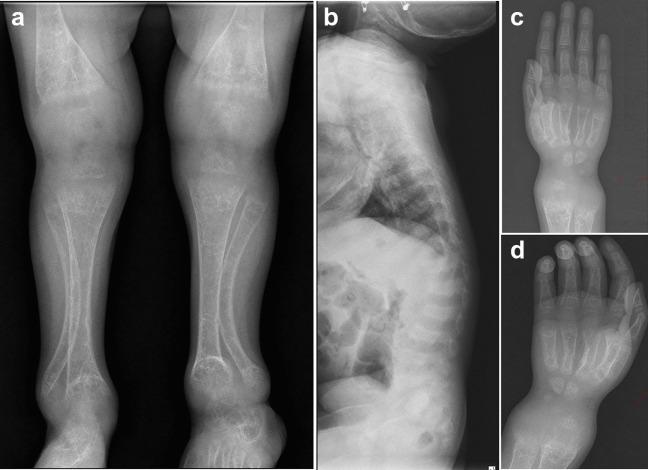

Detailed clinical, radiographic, and biochemical evaluation of 10 families with phenotypes suggestive of a genetic cause of rickets was performed. Molecular testing using exome sequencing aided in the diagnosis of six different forms of known genetic causes.

Eleven disease-causing variants including five previously reported variants (CYP27B1:c.1319_1325dup, p.(Phe443Profs24), VDR:c.1171C>T, p.(Arg391Cys), PHEX: c.1586_1586+1del, PHEX: c.1482+5G>C, PHEX: c.58C>T, p.(Arg20)) and six novel variants (CYP27B1:c.974C>T, p.(Thr325Met), CYP27B1: c.1376G>A, p.(Arg459His), CYP2R1: c.595C>T, p.(Arg199*), CYP2R1:c.1330G>C, p.(Gly444Arg),SLC34A3:c.1336-11_1336-1del, SLC2A2: c.589G>C, p.(Val197Leu)) in the genes known to cause monogenic rickets were identified.